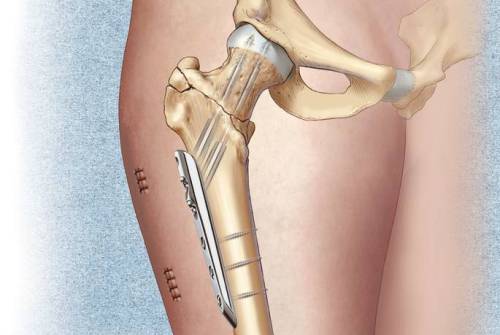

Операция показана если на месте ушиба под кожей скопилась кровь или другие жидкости (выпот, гной). Образование вскрывают и дренируют. Чтобы избежать заражения, назначается антибиотикотерапия. В тяжелых случаях, осложненных вывихом или переломом, врач устанавливает кости на место и при необходимости укрепляет их инструментами металлосинтеза.

После сопоставления частей кости их могут скреплять остеосинтезом.

Недуг рекомендуют лечить хирургически при наличии обширного кровоподтека в травмированной зоне. Хирург вскроет гематому, удалит мускульный детрит и кровяные сгустки, сделает дренирование полости.